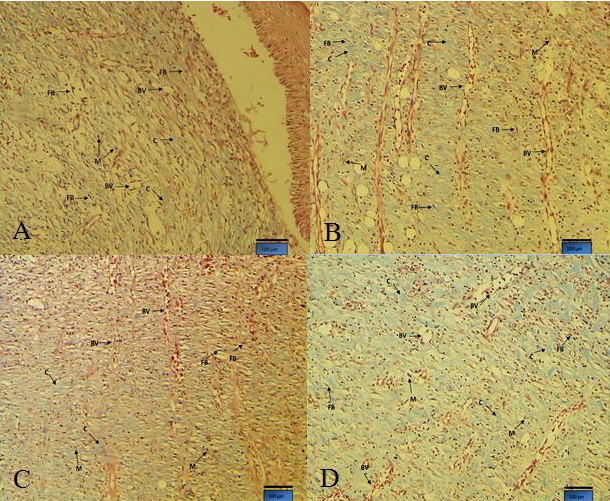

Results of the quantitative and qualitative studies the parameters involved in excision wound healing, in sample tissue slides in 3rd, 7th, 14th and 21th days after wound creation are presented in table 2 and figure 1, respectively. In histological evaluation of 1.5, 3 and 6 percent TRO treated groups on the 14th day after excision wound creation, the tissues demonstrated by the high newly formed blood capillaries (angiogenesis) (Table 3) to significant increase in neovascularization, fibroblast migration and higher collagen deposition (more intense blue coloration) in 6% treated group (Fig. 1D), compared to control group (Fig. 1A).

Fig. 1: cross section from tissue 14 days after wound induction in (A) control-sham group, (B) TRO 1.5%, (C) TRO 3%, (D) TRO 6% groups in Rat.

Note well formed collagen in deep dermis and longituneal angiogenesis in treated animals. Hgih dose of TRO dependently downregulated the immune cells infiltration and enhanced collagen deposition in comparison to control-sham animals, Masson trichrom staining, 400×. Note: Fibroblasts (FB), Macrophages (M), Collagen (C) bundles and vascularization with new blood vessels (BV).